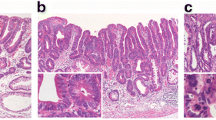

LS was defined as in a previous study [17]. In brief, LS+ regions had small carcinoma cells confined to the stroma at the gland-neck level that gradually differentiated to signet ring cells in the superficial (and deep) lamina propria (Figure 1a). The absence of LS in intramucosal regions of the tumour was defined by four patterns: 1) contact of small carcinoma cells to the muscularis mucosae in SIG, 2) mucinous adenocarcinoma, 3) POR and 4) the presence of a TC (Figure 1b-f).

Histological appearances of intramucosal parts of undifferentiated-type gastric carcinomas (UGCs). A signet ring cell carcinoma (SIG) component with a layered structure in case A107 (a). Small carcinoma cells are distributed in the deeper part just above or in the muscularis mucosae in a SIG component in case M109 (b). A mucinous adenocarcinoma component in case A107 (c). A poorly differentiated adenocarcinoma component in case SM106 (d). Minor tubular components in cases SM105 and SM201, respectively (e, f).